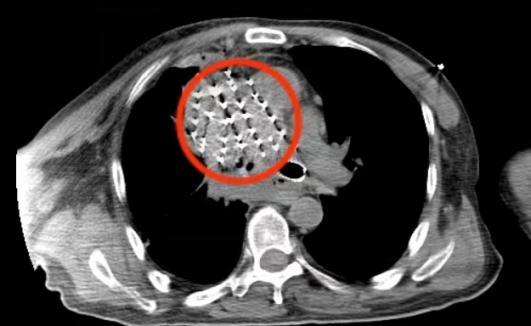

面对终末期肺癌患者气道阻塞与肿瘤持续进展的双重困境,传统单一治疗手段难以兼顾快速缓解呼吸症状与长期控制肿瘤进展。我院呼吸与危重症医学科迅速启动多学科协作机制,制定精准诊疗路径:通过定制气管Y型支架即刻恢复气道通畅,为后续治疗赢得关键时间窗;同步实施CT引导下放射粒子植入术,将碘125粒子精准植入肿瘤内部,实现持续低剂量靶向照射,肿瘤控制率高,显著降低再阻塞风险;同时联合胃镜引导空肠营养管置入,强化全身营养支持。术后患者呼吸功能快速改善,气促、咳嗽症状明显缓解,恢复日常活动能力,目前已出院。

CT下碘125粒子植入